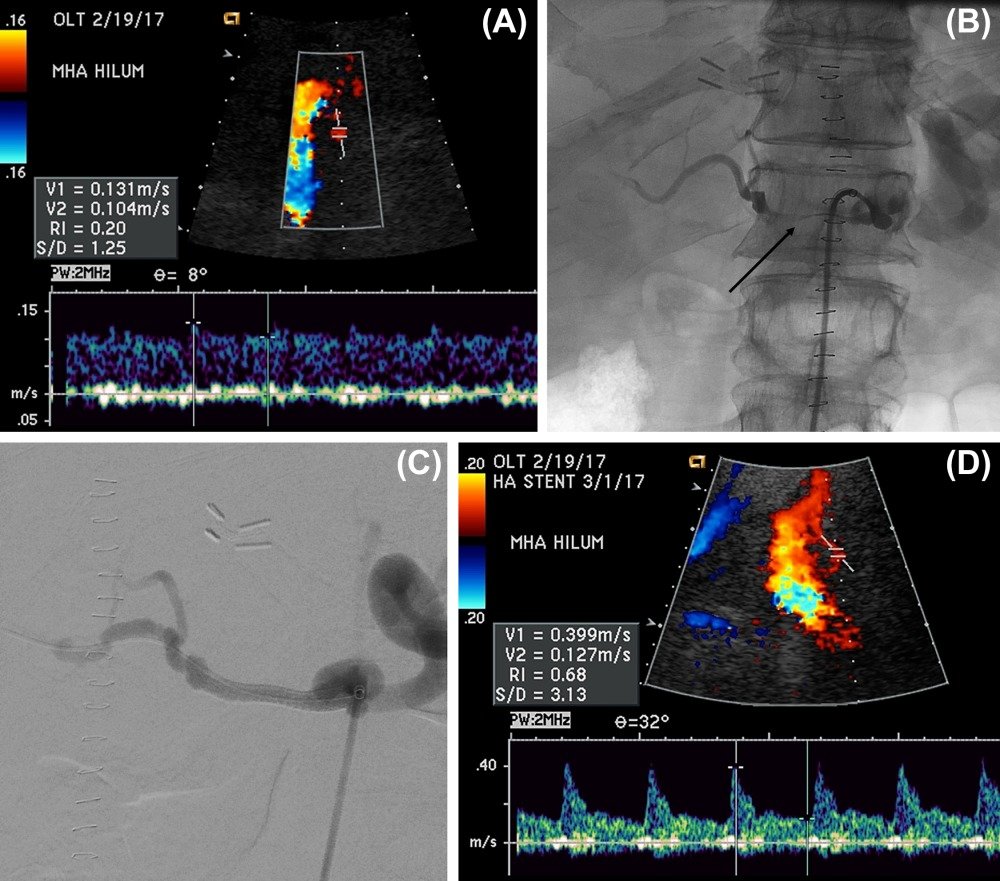

The authors discuss how IR can help manage hepatic artery thrombosis and hepatic artery stenosis.